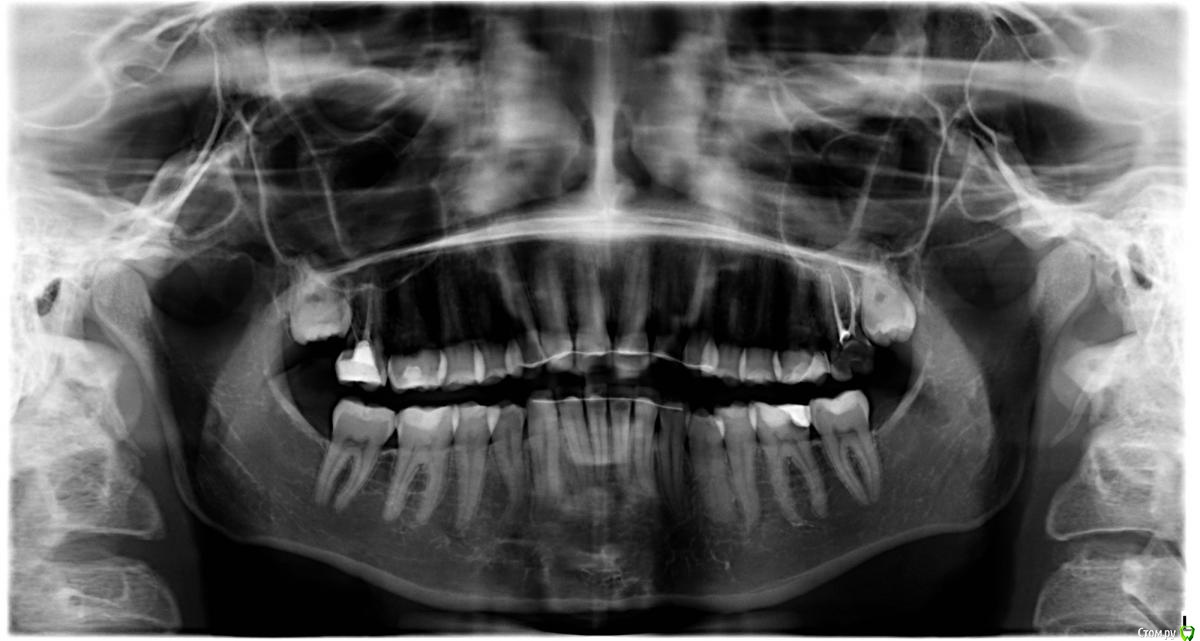

neuromancer Опубликовано 2 апреля, 2015 Поделиться Опубликовано 2 апреля, 2015 Здравствуйте!Болит верхний крайний правый зуб с задней стороны при чистке зубов. Каналы в нем пролечены очень давно (больше 6 лет назад). Один стоматолог говорила, что проблема может быть в самой пломбе и десне (зуб трогать не надо), второй сделала снимок и советует только удаление и протезирование. Я больше доверяю второму, но хочу уточнить, нельзя ли сохранить зуб? И если нельзя, как срочно нужно удалять? Хотелось бы хотя бы полгода проходить без протезирования, так как долечивать, возможно, придется уже в другом городе. Ссылка на комментарий

Гарриевич Опубликовано 2 апреля, 2015 Поделиться Опубликовано 2 апреля, 2015 (изменено) Сделайте прицельный снимок интересующего зуба Изменено 2 апреля, 2015 пользователем Гарриевич Ссылка на комментарий